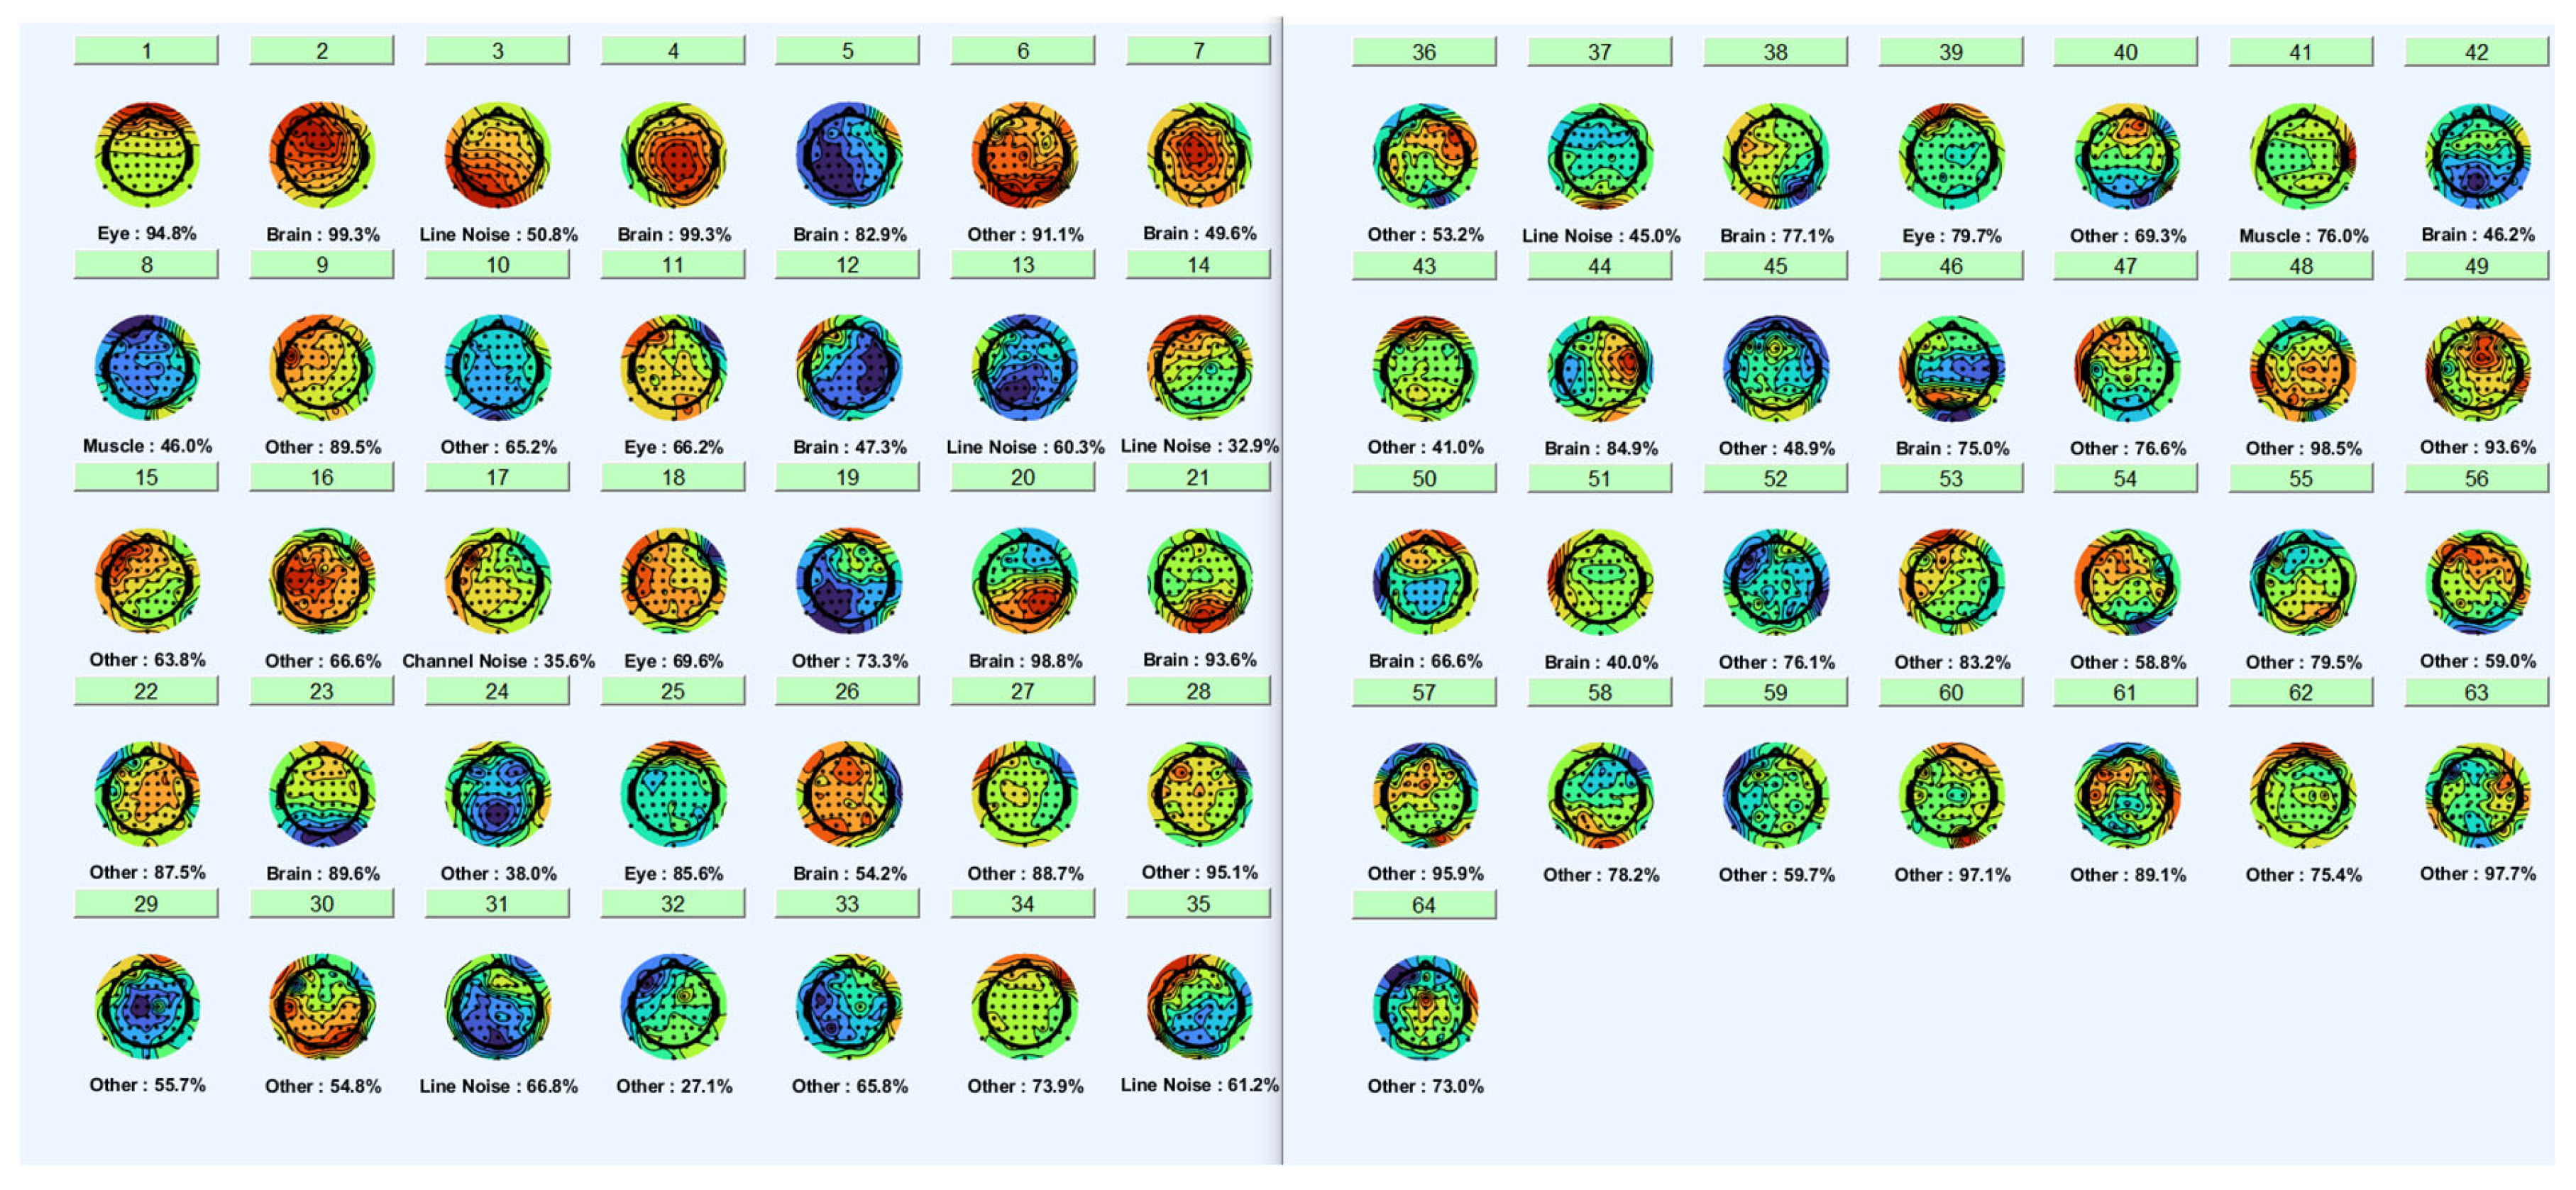

2. Materials and Methods

2.5. Classification

3. Results

3.1. Classification Results